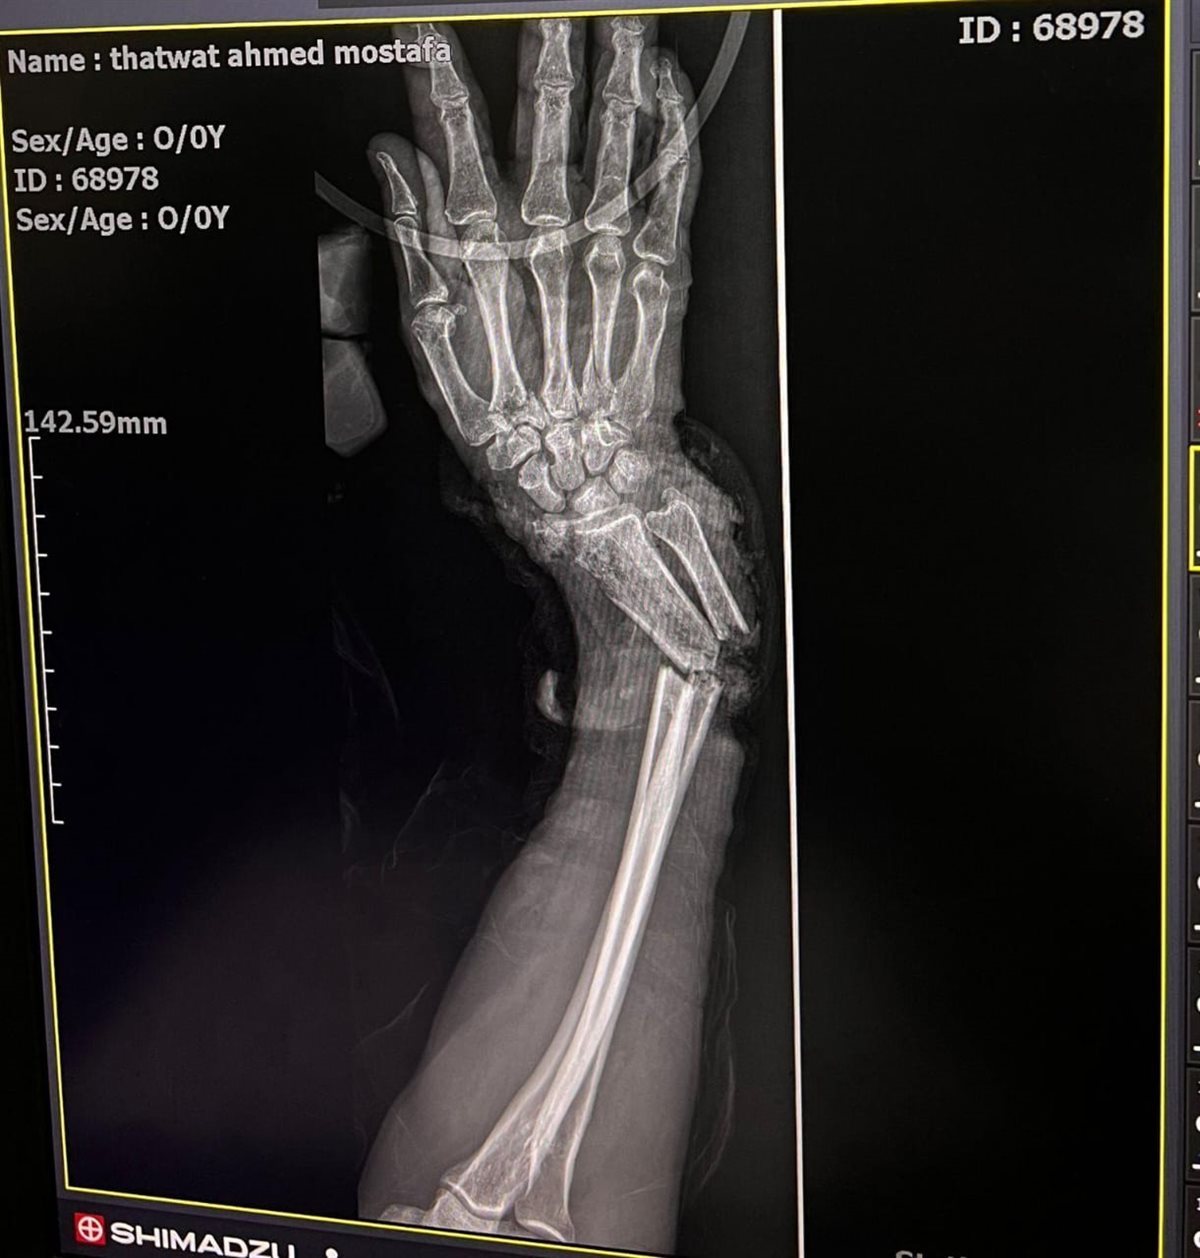

وقال الدكتور ياسر عثمان مدير وحدة الجراحات الميكروسكوبية أن التنسيق بين الفرق المختلفة كان عنصرًا حاسمًا في نجاح التدخلين، موضحاً أن الحالة الأولى كانت لمصاب يبلغ 52 عامًا أصيب في حادث قطار، نتج عنه بتر أسفل الساعد الأيمن مع قطع كامل للأوتار والشرايين والأعصاب، إضافة إلى كسر مضاعف بالكعبرة والزند، وقد تم خلالها إعادة توصيل الأوتار والأعصاب والشرايين وتثبيت الكسور بواسطة شريحة ومسامير، والحالة الثانية لمصاب يبلغ 23 عامًا تعرض لحادث سيارة أدى إلى بتر أعلى العضد الأيسر وقطع تام للشرايين والأعصاب والعضلات مع كسور مضاعفة بالساعد، وتم خلالها تثبيت الكسور وإعادة توصيل الشريان العضدي باستخدام رقعة وريدية